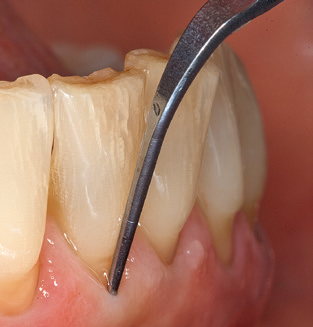

Of course, working tips for the cleaning of implant surfaces are also indispensable for SPT in patients fitted with implants. The implant cleaning attachment on the system used here is characterised by its tapered, hexagonal design. This design allows light, atraumatic penetration of the peri-implant pocket and displays a good cleaning performance (Fig. 7).

Fig. 4: Flexible probes with millimetre markings are recommended for the probing of dental implants (e.g. Colorvue Kit PCV11KIT6, Hu­Friedy). – Fig. 5a and b: A straight working tip (1P, W&H Dentalwerk Bürmoos GmbH) is a suitable instrument for use on all natural teeth. – Fig. 6: Curved working tips (3Pr/3Pl, W&H Dentalwerk Bürmoos GmbH) lend themselves to the processing of difficult-to-reach areas of the tooth and root surfaces (e.g. furcations). – Fig. 7: The tapered, hexagonal implant cleaning tip (1I, W&H Dentalwerk Bürmoos GmbH) permits atraumatic and efficient cleaning of the crown and abutment surfaces. – Fig. 8: Titanium and carbon curettes are suitable instruments for the manual cleaning of the implant surfaces.